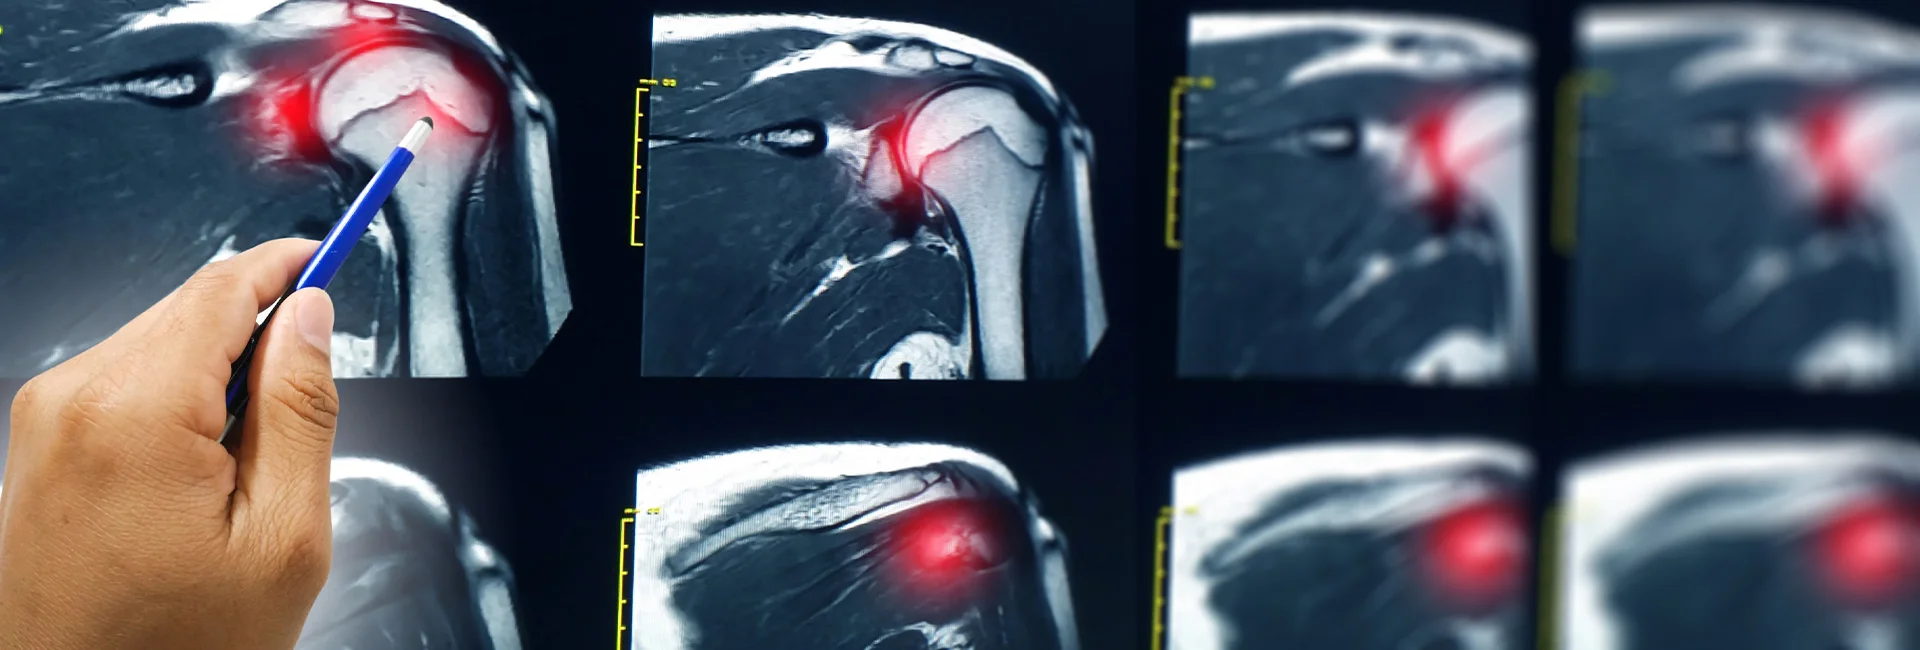

Az MR vizsgálat segítségével a legapróbb eltérések is láthatóvá válnak, ami a hagyományos röntgenfelvétellel, vagy ultrahanggal nem mindig lehetséges. Így számtalan esetben a diagnózis sokkal pontosabb lehet, a kezelés pedig célzottabbá válik. Legyen szó sportsérülésekről, ízületi problémákról, rotátroköpeny-szindrómáról vagy akár komolyabb egészségügyi kérdésekről, az MR vizsgálat eredménye a betegségek és állapotok mélyebb megértéséhez vezethet.

Miután elmeséltem Major Bálint doktor úrnak vállam történetét, a fizikális vizsgálat következett. Megnézte a vállam mozgásait, erősségét. Ahhoz, hogy tökéletes diagnózist fel tudjon állítani elküldött egy váll röntgen vizsgálatra is. Mivel a röntgen főleg a csontok állapotáról ad képet, ezért váll MR vizsgálatot is kért. Bár sokan beszélnek róla, és már számtalan ismerősöm is átesett MR vizsgálaton, én mégis tele voltam kérdésekkel. Érdekelt, mit mutat ki pontosan az MR és hogyan járul hozzá a vállam állapotának javulásához. Szerettem volna minél előbb újra egészséges lenni, ezért alig vártam az MR vizsgálat időpontját.